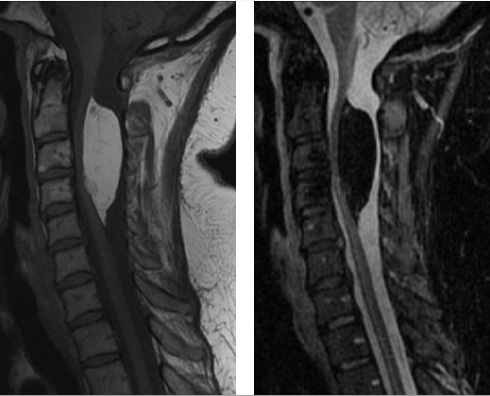

Seorang wanita 47 thn datang dengan parestesia di kedua lengan dan leher serta nyeri bahu sejak kecil. MRI tulang belakang cervcal menunjukkan (T1– left, STIR– right). Apakah diagnosis yg plg mungkin?

E. Lipoma

The correct answer is lipoma.

The MRI shows an intradural extramedullary mass which is fairly homogenous and is T1 hyperintense and STIR hypointense. The STIR sequence suppresses fat signal, suggesting that this mass is composed of fat. The other answer choices are lesions which are either not composed of fat or not found in the intradural extramedullary space.